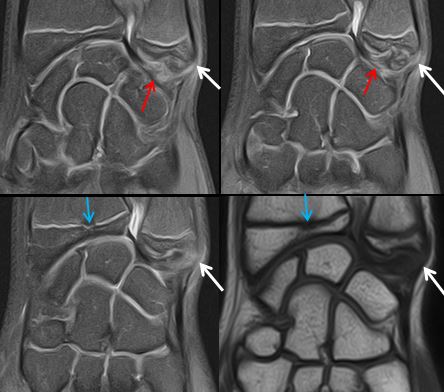

Lésions ligamentaires du poignet

Traumatisme du poignet à radiographie normale